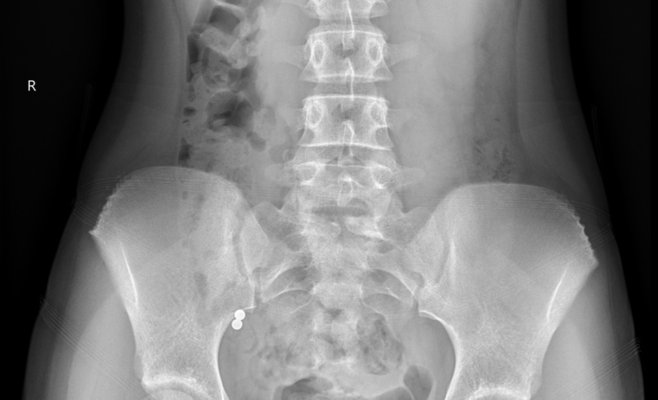

Одному из пациентов повезло — магнитные шарики вышли естественным путём, не вызвав осложнений. Однако другие дети до сих пор остаются в больнице, и двум из них требуется срочная операция. Рентгеновские снимки, опубликованные больницей, показывают, что у некоторых детей внутри тела оказалось до пяти магнитных шариков, что может привести к серьёзным повреждениям внутренних органов.